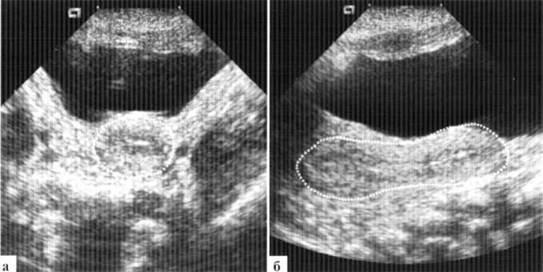

Матка новорожденной может достигать размеров 20 (длина)х2() (ширина)х15 (толщина) мм с толщиной М-эха до 5 мм. Неонатологам хорошо известны клинические проявления так называемого «полового криза» новорожденных, в том числе и кровянистых выделений из влагалища. Такие особенности строение внутренних гениталий также связаны с гормональным фоном ребенка, особенностями гормонального фона матери, наличием или отсутствием грудного вскармливания. В норме у новорожденной девочки шеечно-маточный угол не выражен, толщина тела и шейки матки практически одинаковая и граница между ними видна нечетко, соотношение длины тела матки к шейке — около 1:2 (рис. 1.3).

Рис. 1.3. Матка здоровой новорожденной (контур обведен пунктиром): а — фронтальный скан; б— сагиттальный скан